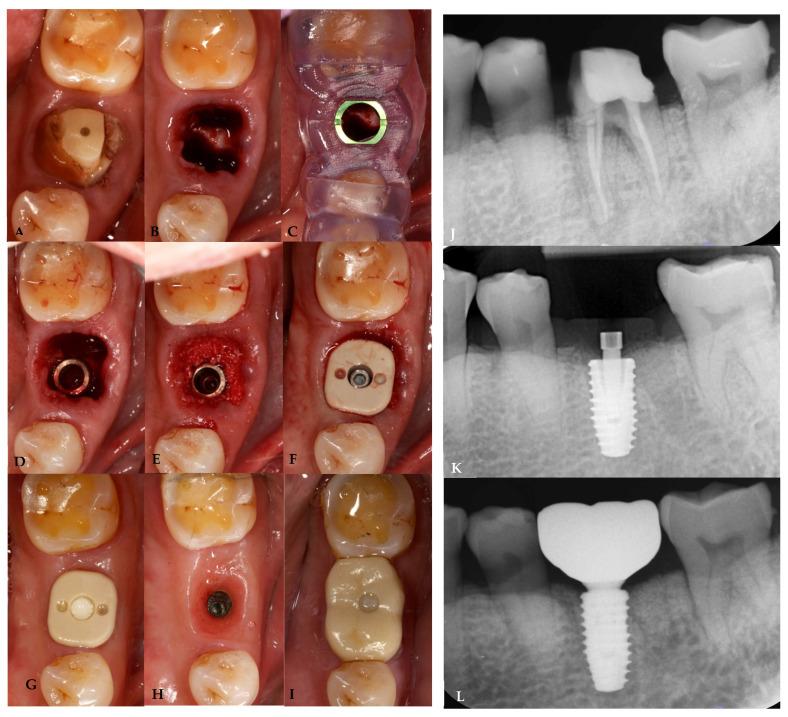

This study aimed to evaluate the effect of customized healing abutments compared to prefabricated healing abutments in immediate implant sites. Twelve patients requiring single immediate implant placement were divided into two groups: a prefabricated group received prefabricated titanium healing abutments, and a customized group received a polyetheretherketone (PEEK) customized healing abutments fabricated based on the individuals' digital impressions. Outcomes, including peri-implant horizontal and vertical soft tissue alteration, bone level change, volume change, pain score, and pink esthetic score (PES) change, were evaluated at the 1-, 4-, and 6-month follow-ups compared to pre-extraction teeth. At the 1- and 4-month follow-ups, the customized group had a significantly lower buccal volume variation (BVv). At the 6-month follow-up, neither group showed any significant difference in the marginal bone change; however, the customized group had a significantly lower PES change and a lower pain score. In the anterior and premolar regions, the customized group showed the preservation of peri-implant buccal horizontal soft tissue and buccal volume, while in the molar regions, the preservation of papilla height and midfacial height was observed. The morphology of the customized healing abutment demonstrated a better trend in preservation of peri-implant soft tissue, esthetic outcomes, and lower patient discomfort in immediate implant sites.

本研究旨在评估在即刻种植位点使用定制愈合基台与预制愈合基台相比的效果。12例需要进行单颗即刻种植的患者被分为两组:预制组接受预制钛愈合基台,定制组接受基于个体数字化印模制作的聚醚醚酮(PEEK)定制愈合基台。与拔牙前的牙齿相比,在1个月、4个月和6个月的随访中评估各项结果,包括种植体周围水平和垂直软组织变化、骨水平变化、体积变化、疼痛评分和粉色美学评分(PES)变化。在1个月和4个月的随访中,定制组的颊侧体积变化(BVv)显著更低。在6个月的随访中,两组在边缘骨变化方面均未显示出任何显著差异;然而,定制组的PES变化显著更低且疼痛评分更低。在前牙区和前磨牙区,定制组显示出种植体周围颊侧水平软组织和颊侧体积得以保留,而在磨牙区,则观察到龈乳头高度和面部中部高度得以保留。定制愈合基台的形态在即刻种植位点的种植体周围软组织保留、美学效果以及降低患者不适感方面呈现出更好的趋势。